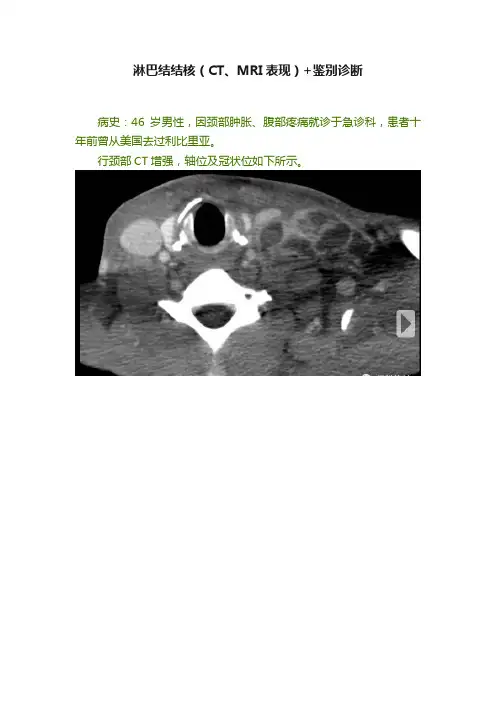

淋巴结结核(CT、MRI表现)+鉴别诊断病史:46岁男性,因颈部肿胀、腹部疼痛就诊于急诊科,患者十年前曾从美国去过利比里亚。

行颈部CT增强,轴位及冠状位如下所示。

影像表现:颈部、纵隔、肺门、腹腔及腹膜后见多发坏死性肿大淋巴结。

(补充:增强扫描呈环形强化)鉴别诊断:•淋巴结结核•淋巴瘤•转移癌•结核分枝杆菌感染•非结核分枝杆菌感染•播散型组织胞浆菌病感染•惠普尔病•自身免疫性疾病(如:系统性红斑狼疮)诊断:淋巴结结核(活检证实)背景:•结核(TB)通常局限于呼吸系统;•然而,也可以累及其它器官,免疫缺陷人群更易患肺外结核;•超过95%的儿童及超过40%的成人结核患者影像学可发现淋巴结肿大;•婴儿常常仅表现为淋巴结肿大,这种情况随年龄增加而减少。